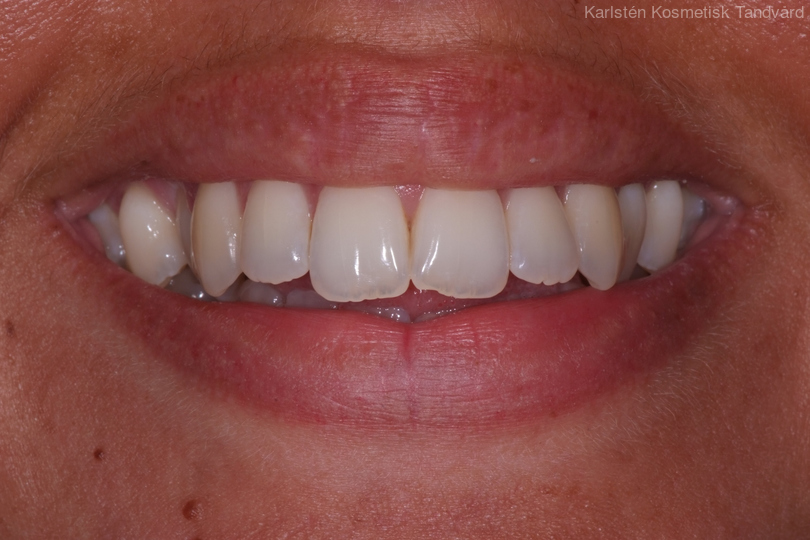

Ung kvinna som tidigare haft tandreglering. Upplever inte att tänderna står i en fin tandbåge. 11 månaders behandling med genomskinliga Invisalignskenor resulterade i ett fint leende.